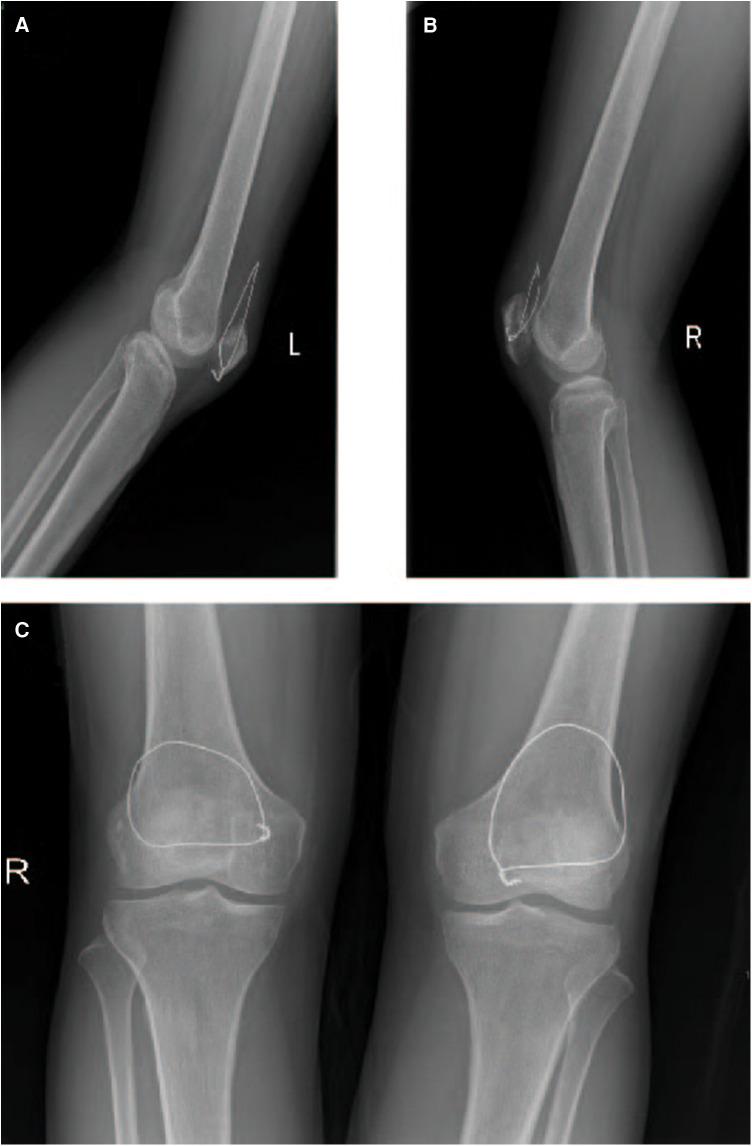

The quadriceps tendon, crucial for body movement, is among the body's strongest tendons. Factors like diabetes or hormone use can weaken it, making even minor trauma potentially causing rupture. Bilateral spontaneous quadriceps tendon rupture, where both tendons tear simultaneously, is rare. Prompt diagnosis and treatment are crucial. We present a case of a 44-year-old woman who experienced bilateral rupture after falling while doing chores. She had immediate pain and limited knee movement. Diagnosis via physical examination and CT/MRI scans confirmed the rupture. Surgical repair followed by rehabilitation led to significant pain reduction and improved function within two months. Overall, her postoperative outcome was satisfactory. This study underscores the importance of clear diagnosis, timely surgery, and thorough rehabilitation for optimal patient recovery from bilateral quadriceps tendon rupture.

股四头肌肌腱对身体运动至关重要,是人体最强壮的肌腱之一。糖尿病或激素使用等因素会使其变弱,即使是轻微创伤也可能导致破裂。双侧自发性股四头肌肌腱破裂,即两条肌腱同时撕裂的情况很少见。及时诊断和治疗至关重要。我们报告一例44岁女性病例,她在做家务时摔倒后发生双侧破裂。她立即感到疼痛,膝关节活动受限。通过体格检查和CT/MRI扫描确诊为破裂。手术修复后进行康复治疗,两个月内疼痛显著减轻,功能得到改善。总体而言,她的术后结果令人满意。本研究强调了明确诊断、及时手术和全面康复对于患者从双侧股四头肌肌腱破裂中最佳恢复的重要性。